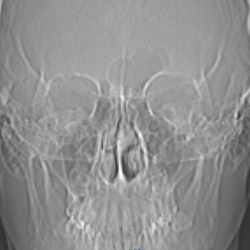

Добрый день. Помогите пожалуйста. слева синусит или образование ? деструкция костной стенки левой ВЧП?